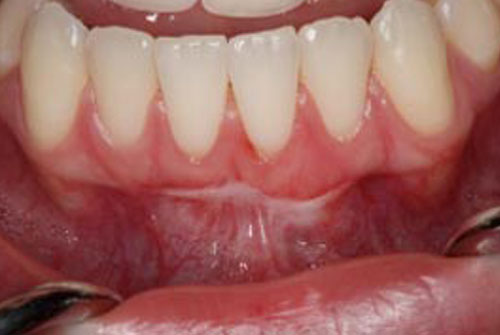

• Free Gingival Graft

Cook Periodontics in Wilmington and Leland, NC specializes in gum grafting to treat recession. Also known as soft tissue grafting, this procedure is performed when there is major gum recession or exposed tooth roots. Tissue is taken from a healthy area of the mouth and then grafted to the area where it is missing or lacking.